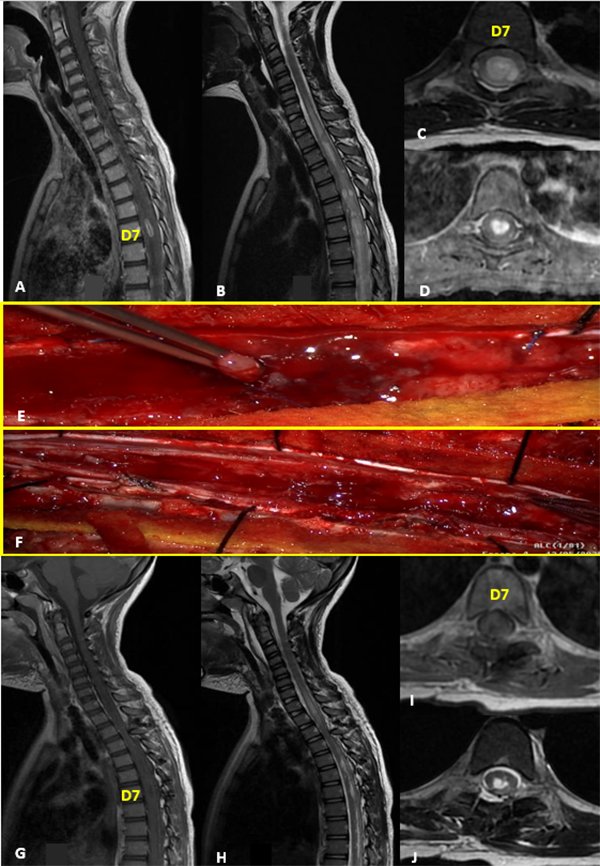

VI: Tumor Glioneuronal con islotes Neuropil-like

Paciente sexo masculino de 12 años sin antecedentes patológicos que consulta por déficit sensitivo y motor en hemicuerpo derecho de 2 años de evolución. Al examen físico presenta hipotrofia e hipoestesia derecha asociado a paresia leve del miembro superior derecho. La RM evidenció lesión expansiva intramedular sólido quística que se extendía desde C3 hasta C7 con marcado engrosamiento del cordón medular a predominio derecho; hiperintensa en T2 e isointensa en T1 con gran realce heterogéneo tras la administración de contraste endovenoso. Además presentaba otra lesión quística a nivel de D2. Se realizó exéresis completa de la lesión cervical. El monitoreo neurofisiológico intraoperatorio registró una caída del 30% de la onda D y un descenso leve de los potenciales motores. El McCormick postoperatorio inmediato empeoró a grado 4, mejorando progresivamente en las semanas subsiguientes con kinesiología hasta alcanzar el estado funcional previo. La anatomía patológica intraoperatoria por congelación informó astrocitoma pilocítico, que posteriormente fue modificada a tumor glioneuronal con islotes neuropil-like (Grado III de la OMS). Dicha lesión presenta un patrón de presentación infrecuente con áreas de tipo pilocíticas y otras de mayor densidad celular con leve pleomorfismo nuclear y un índice de proliferación relativamente elevado. La RM control reveló resección completa tumoral con realce leptomeníngeo difuso a predomino de la unión bulbo-medular, cervical, dorsal alto y epicono posterior sugestivo de diseminación meníngea (Figura 6).

Figura 6:

Tumor Glioneuronal con islotes Neuropil-like. A-D: RM prequirúrgica T1 con contraste y T2 cortes axiales y sagitales. E-F: Imágenes intraoperatoria pre y postresección. Se señala expresión cortical derecha de lesión (flecha roja) que desplaza rafe medio (flecha negra). G-J: RM postquirúrgica T1 con contraste y T2 cortes axiales y sagitales.